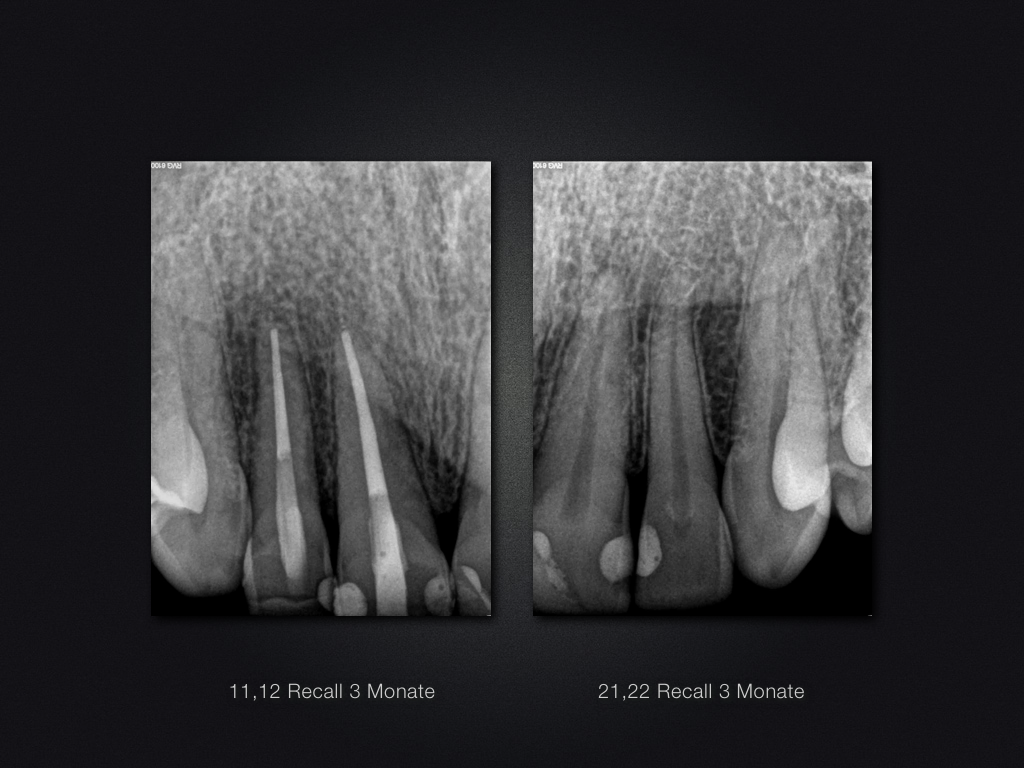

11,12 D Recall.014 Veröffentlicht 4. März 2016 am 1024 × 768 in Trauma „Zweitversorgung“ – das Recall